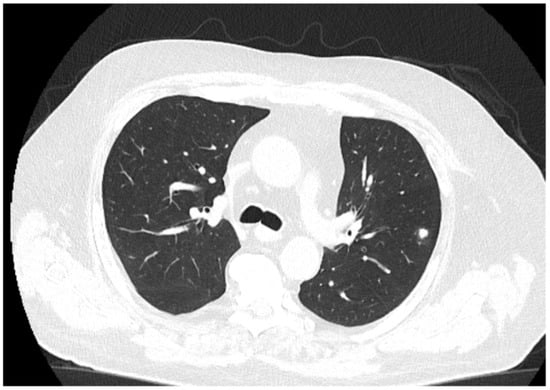

The patient received a follow-up brain MRI and chest CT (Figure 6) at 3 months, which showed complete remission of the brain abscess.

Figure 6. Follow-up Ct at three months. The chest CT does not show any cavitating lesions, with residual scarring and healing processes of the lesions.